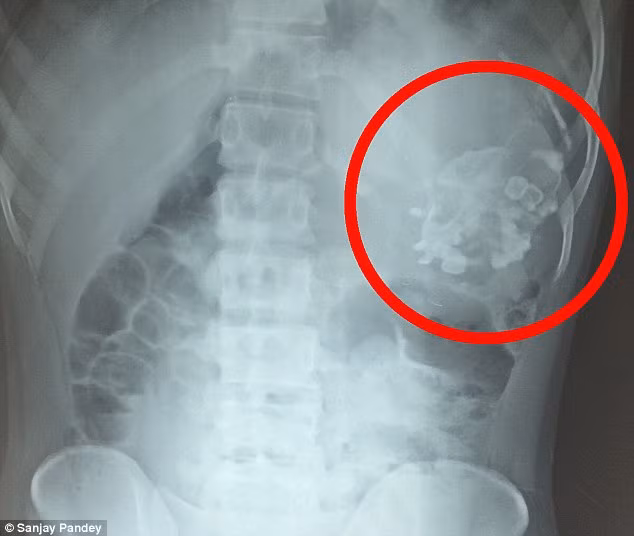

Anh chàng 18 tuổi Narendra, người Ấn Độ đã bị đau bụng kinh niên phải nhập viện. Tại đây, các bác sỹ vô cùng sốc khi phát hiện một bào thai chết lưu ký sinh nặng 2,5kg chứa đầy răng và tóc trong bụng anh.

Ca phẫu thuật kéo dài 3 giờ đồng hồ, các bác sỹ đã loại bỏ một bào thai chết lưu của một em bé có răng, tóc và đầu không phát triển, có cấu trúc xương ngực, cột sống và rất nhiều ối màu vàng lỏng.

Đây được gọi là hiện tượng "thai trong thai", hay còn gọi là song sinh ký sinh, rất hiếm gặp trên thế giới, chỉ xảy ra với tỷ lệ 1/500.000 trẻ, hiện mới có khoảng dưới 200 trường hợp mắc hội chứng kỳ lạ này.

Hiện tượng này xảy ra trong giai đoạn đầu người mẹ mang thai cặp song sinh, một thai nhi vào bụng thai nhi còn lại thông qua dây rốn. Do hoàn cảnh mà Narendra đã không đi khám bác sỹ và trường hợp này cũng rất khó chẩn đoán ở giai đoạn đầu.